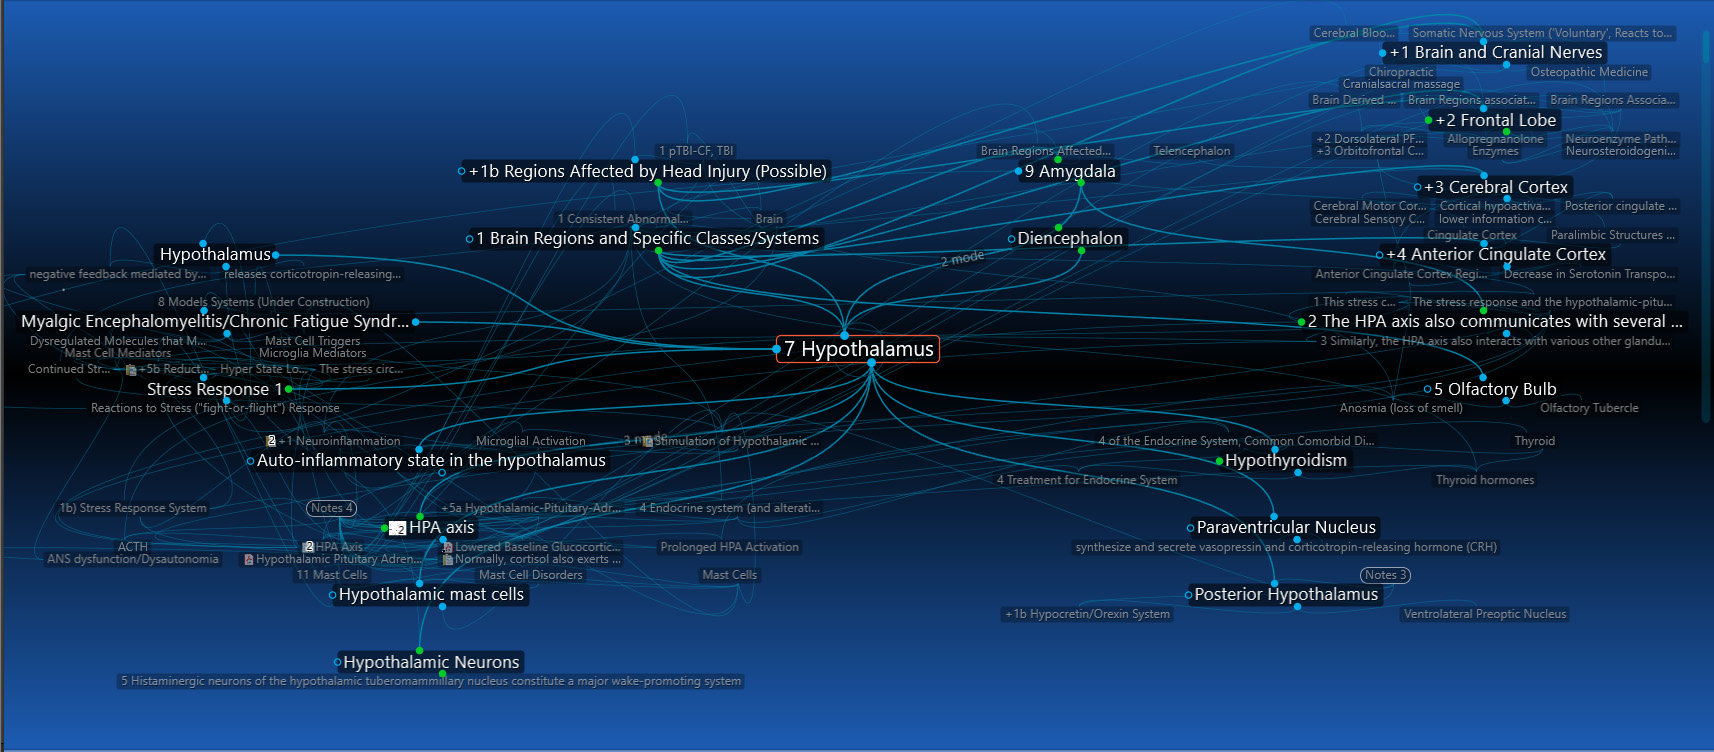

8) Hypothalamus